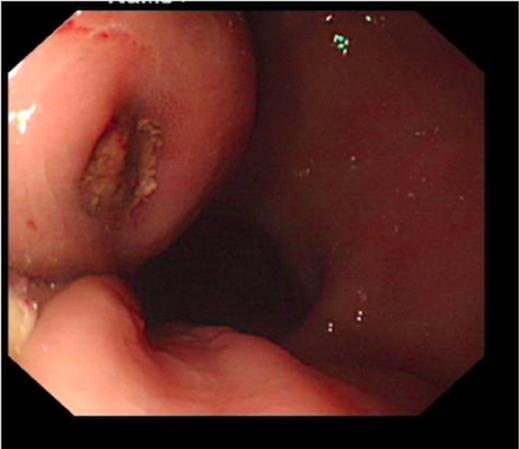

An endoscopy performed four years post-operatively demonstrated two atypical acute gastric ulcers in the distal stomach (figure 1), which were treated with a heat probe (figure 2). Two days later she presented as an emergency in hypovolaemic shock following a large volume haematemesis (haemoglobin of 40g/l). An urgent upper gastrointestinal endoscopy revealed a visible vessel at 35 cm forming part of an expansive mass within the gastric conduit. EUS demonstrated a heterogeneous mass indenting the gastric conduit, containing a strong Doppler signal (figure 3). An urgent computerised tomography (CT) angiogram revealed a Type-A thoracic aortic aneurysm with an enteric fistula (figure 4). The saccular aneurysm of the thoracic aorta was embedded in the gastric conduit. A 28x16cm Valiant® (Medtronic Ltd, Minneapolis, USA) stent was placed in the descending thoracic aorta with good occlusion of the aneurysm. The patient made an excellent recovery and was discharged on the seventh day post stenting.